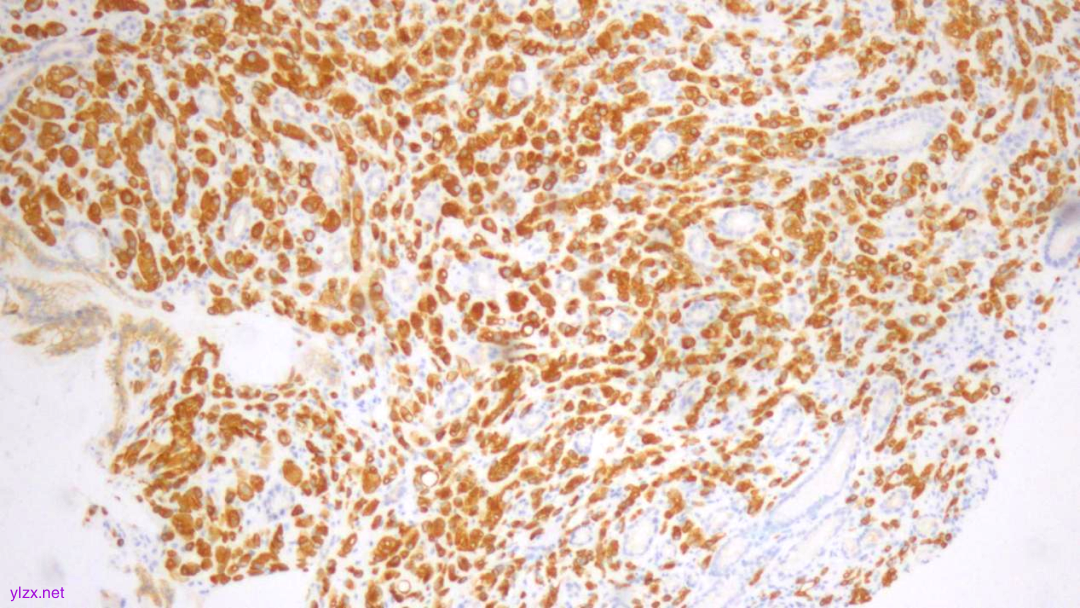

IHC结果:

CK(AE1/AE3)(+)、GATA3(+)、P120(浆+)、E-Cadherin(-)、CK7(+)、CK-H(+)、CAM5.2(+)、CK20(-)、CEA(poly)(-),P53(约40% 弱+),Ki-67(约1%+)

AE1/AE3(弥漫强+)

GATA-3(+)

P120(浆+)

E-Cadherin(-)

CEA(少量+)

CK7(弥漫强+)

ki-67(个别细胞+)

(胃窦)腺癌,HE形态结合临床病史、免疫组化结果,符合乳腺浸润性小叶癌转移。